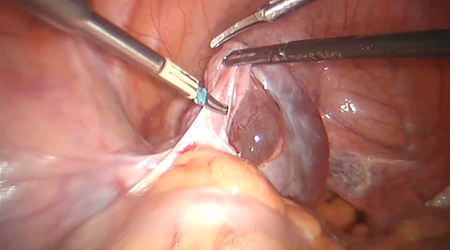

Operacijos metu rasta riestinės žarnos sąaugų su pilvo siena, iš dalies dengiančių kairiuosius gimdos priklausinius. Sąaugos išdalytos naudojant robotines žirkles. Rastas 7 cm skersmens kairės kiaušidės cistinis darinys. Dešinėje kiaušintakio nerasta. Dešinė kiaušidė ir gimda – vizualiai nepakitusios. Kairė salpingoovarektomija atlikta identiškai laparoskopinės operacijos technikai: atvertas kairysis retroperitoninis tarpas, vizualizuotas kairysis šlapimtakis, koaguliuotas ir perkirptas kairysis kiaušidės pakabinamasis raištis kartu su kiaušidės arterija ir vena (žr. 1 pav.), kairysis kiaušidės nuosavasis raištis ir kairysis kiaušintakis. Kairysis gimdos priklausinys iš pilvo ertmės pašalintas su endomaišeliu per supraumbilikalinę troakaro angą (žr. 2 pav.). Pilvo ertmė nedrenuota.

1 pav. Kairysis kiaušidės pakabinamasis raištis koaguliuotas ir perkirptas kartu su kiaušidės arterija ir vena